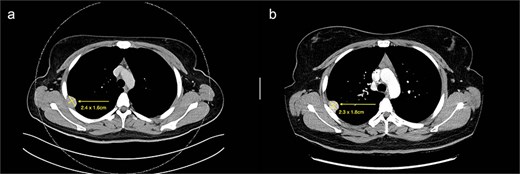

We present a case of a 25-year-old female with a known primary adenocarcinoma of the ascending colon. During staging CT imaging in April 2024, she was found to have a solitary, well-circumscribed right upper lobe pleural nodule (2.4 × 2.1 cm) (Fig. 1a). A CT-guided core biopsy was performed to differentiate between metastatic disease and a second primary lesion. Histopathological analysis revealed a mesenchymal tumour harbouring a novel NCOR2(exon 7)::GLI1(exon 6) gene fusion. This particular fusion has not been previously documented in the literature, making it a noteworthy diagnostic finding.

(a) Axial cut of CT thorax taken in April 2024, depicting a right sided hyperdense peripheral pleural lesion measuring 2.4 × 1.6 cm. (b) Axial cut of a repeat CT thorax taken in February 2025, showing the same hyperdense pleural lesion relatively stable in size, now measuring 2.3 × 1.8 cm.

From a clinical perspective, given the uncertain malignant potential of GLI1 fusion-associated tumours, and in the context of her ongoing adjuvant chemotherapy (8 cycles of XELOX for 6 months) for colorectal adenocarcinoma, surgical management of the pleural lesion was deferred. Serial imaging over 10 months demonstrated tumour stability in size (2.3 × 1.8 cm), suggesting indolent behaviour (Fig. 1b). However, in view of the histological ambiguity and lack of established prognostic markers, despite the seemingly benign behaviour, a shared decision was made to proceed with surgical excision.